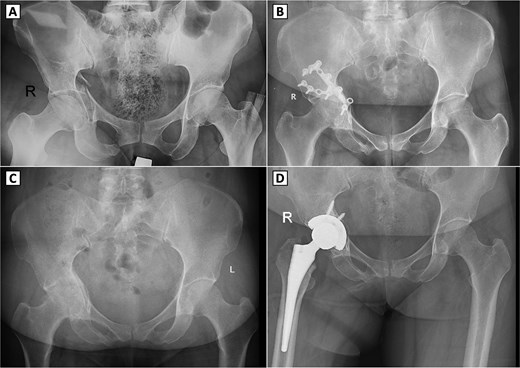

A 49-year-old female sustained a right acetabular fracture from a fall and underwent ORIF via an anterior approach without immediate complications (Fig. 1A and B). The patient resumed ambulation with intermittent hip pain and did not require analgesics. At nine months post-ORIF, radiographs confirmed bony union but revealed secondary osteoarthritis (Kellgren-Lawrence grade III), with joint space narrowing, femoral head deformity, and subchondral sclerosis (Fig. 1C). Clinically, she had a limping gait, restricted hip range of motion (ROM: 98° flexion, 9° extension, 39° internal rotation, 41° external rotation, 42° abduction, and 10° adduction), yet retained squatting and leg-crossing abilities. Neurological examination and scar healing findings were unremarkable. Due to osteoarthritis progression, the hardware was removed via the anterior approach, but hip function remained unchanged. Seven months later, radiographs showed healed screw holes but advanced osteoarthritis (Kellgren-Lawrence grade IV). THA was performed via a direct lateral approach (Fig. 1D), using techniques akin to primary THA, as prior hardware removal cleared the surgical field without significant bone defects. Post-THA, immediate weight-bearing and physiotherapy were initiated, with no complications. Two years post-THA, hip function improved markedly without complications.

Serial radiographs of a patient with right acetabular fracture treated with open reduction and internal fixation (ORIF), followed by secondary osteoarthritis and conversion to total hip arthroplasty. (A) Preoperative anteroposterior (AP) pelvic X-ray showing a displaced right acetabular fracture. (B) Postoperative AP radiograph demonstrating internal fixation with reconstruction plates and screws on the right acetabulum. (C) Follow-up AP pelvic radiograph showing signs of secondary osteoarthritis in the right hip joint, showing shows signs of secondary osteoarthritis in the right hip joint, including joint space narrowing, femoral head deformity, and subchondral sclerosis. (D) Postoperative AP radiograph after conversion total hip arthroplasty with a cementless prosthesis and screw fixation.